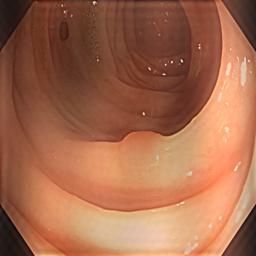

Table I presents our extensive experiments on the polyp segmentation results under FedAvg and FedProx frameworks and benchmarking results with other algorithms. For the metrics defined above, we have highlighted the best-obtained results in bold. Fig. 4 shows samples of the polyp segmentation results. Our comprehensive evaluations reveal that thresholding-based FDG methods (either soft or hard-thresholding) perform better than others.